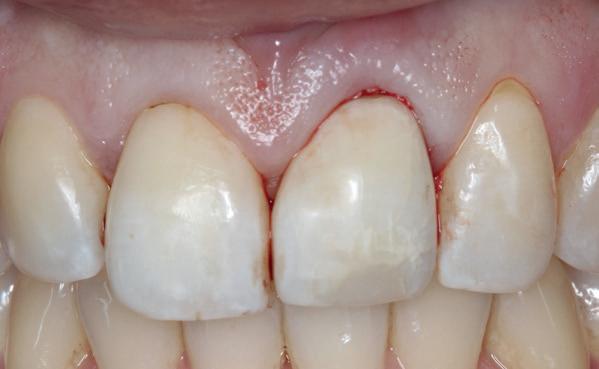

Mevrouw werd naar het Dental Design Center verwezen om een complex probleem aan het bovenfront te beoordelen en indien mogelijk te behandelen. Tien jaar geleden zijn er om esthetische redenen op de 12, 11, 21 en 22 kronen geplaatst. Helaas bleek achteraf een wortelkanaalbehandeling van de 22 noodzakelijk. Na een aantal jaar ontstond er weer een infectie apicaal aan de 22 en werd er een apex uitgevoerd. Helaas had deze behandeling niet het beoogde resultaat. Twee weken voordat ze bij mij op consult kwam, is het element geëxtraheerd en is er een partiële plaat geplaatst als tijdelijke oplossing (foto 1-3).

Na de IPP (esthetisch/functionele) analyse blijkt dat de gezichts- en faciale mediaan niet geheel overeenkomen en dat de gingiva lijnen van het bovenfront niet helemaal parallel lopen met de interpupillaire lijn. Na overleg met mevrouw kiest zij ervoor om dit niet orthodontisch te laten corrigeren. Mevrouw

heeft de nadrukkelijke wens om geen brugconstructie te krijgen. Om die reden is een etsbrug of een conventionele brug geen optie. Daarom bestaat het behandelvoorstel uit vier losse kronen waarvan de 22 implantaat gedragen zal zijn. Een gedetailleerd onderzoek van de regio 22 is noodzakelijk (foto 4-6).

Uit het röntgenonderzoek blijkt dat op de locatie van de 22 veel bot verloren is gegaan en dat er niet direct een implantaat geplaatst kan worden. Om die reden is een botaugmentatie geïndiceerd. Wel zijn distaal van de 21 en mesiaal van de 23 de botpieken aanwezig die de papillen ondersteunen. Naast te weinig bot, is op de locatie 22 in bucco-linguale richting ook te weinig volume gingiva aanwezig. Daarom zal er tevens een soft tissue graft aangebracht worden. Tijdens deze behandeling wordt ook de recessie op de 23 zoveel mogelijk bedekt (foto 7 en 8).